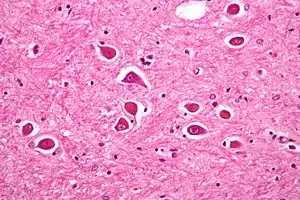

![]() | |

| Micrograph of Alzheimer type II astrocytes, as may be seen in hepatic encephalopathy. | |